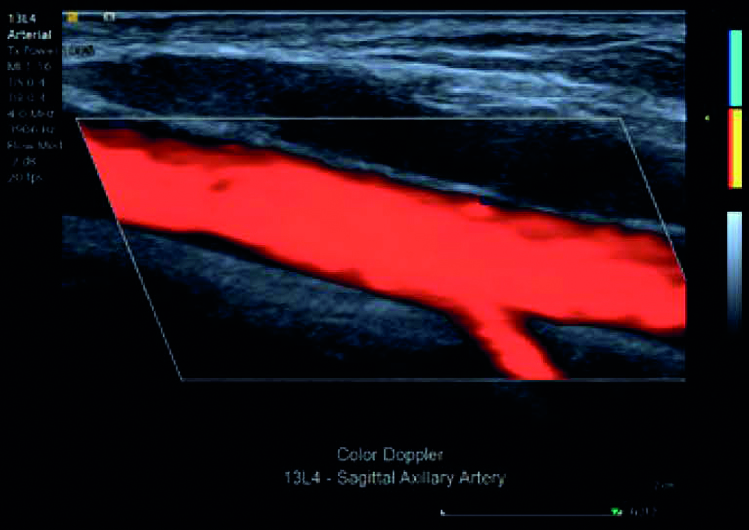

Permette un’eccezionale sensibilità del colore riducendo tutti gli artefatti dovuti al movimento e alla respirazione senza che il medico debba intervenire.